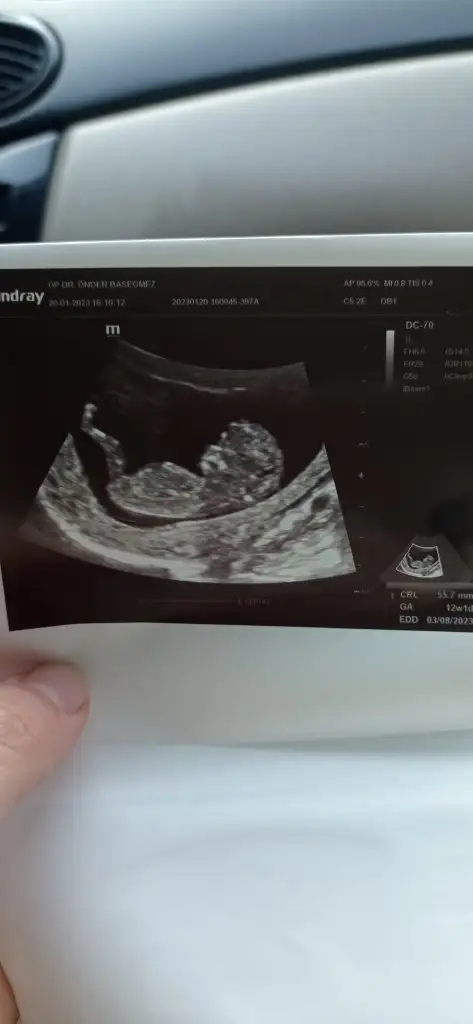

Nub,skull ve cinsiyet

bana da bakar mısınız ☺️

Sizinki nubunu kapatmis ben goremedim ama icime erkek dogdu nedense ilerleyen zamnda giderseniz tekrar foto atarmisiniz

• IMG_20230120_162521.webp

IMG_20230120_162521.webp

17,4 KB · Görüntüleme: 100